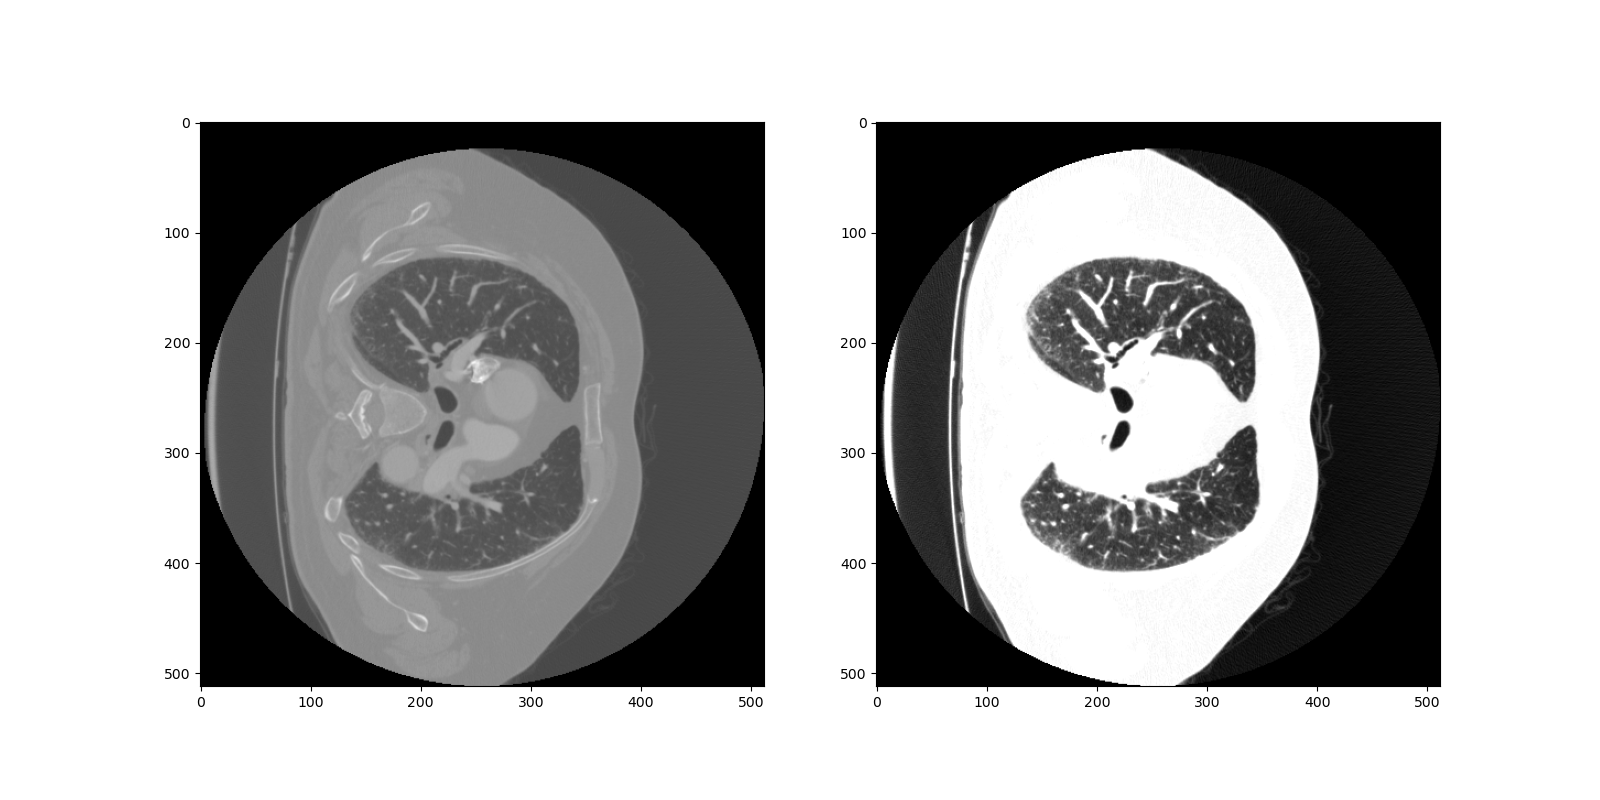

The training and test split in our model AGN is simple. Since the slices of CT scans are sequential, we do not need to shuffle the data to ensure the distributions of various cases in the slices in the training and testing are the similar. Hence, we just take the first 1500 slices as training part. Then, to feed the data into training, we have to do the preprocessing of the data slices. To be more specific, we have to adjust the level and window of the CT scans due to the fact that the Hounsfield ranges are different in different CT scans [2]. In other words, we have to rescale them to the same level. More importantly, we are able to enhance the contrast of the slices through the adjustment. The window and level in our case are 1000 and -600 respectively. Hence, we filter out the units out of the range (-1100, 100), which is illustrated in the Figure 13.

Refer to caption

Figure 13: Preprocessing of the inputs: The left one is the original slice and the right one is the input into the model.